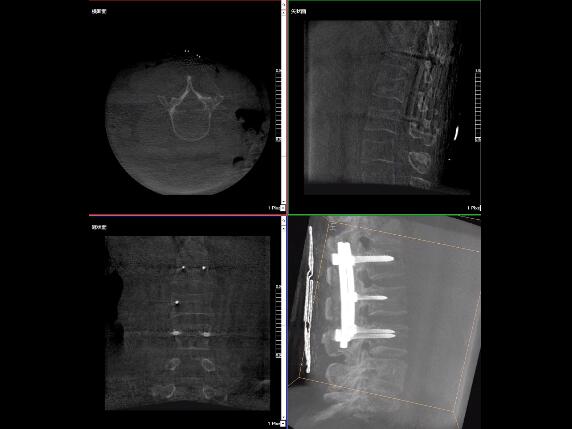

比如,医生在做PKP(椎体成形术)的时候,或者在置入螺钉的时候,医生需要在影像上看到螺钉打进去的进针点以及进针的路径。比如,我们在打腰椎的钉子时需要看到“猫眼”。我们只有把钉子完全打在“猫眼”里面,才能确保钉子打在了椎弓根里,所以对“猫眼”的显影就非常重要。

“猫眼”指的是椎弓根在正位的投影。

最后我要强调一点,以上我提到的“猫眼”,在二维的X光片上,医生是靠经验去判断钉子是否打在椎弓根里,这个时候如果我们的设备再先进一点,诊断手段再多一点,如果我们能够把二维的影像转换为三维的影像,可能就不会完全依赖医生的经验。

我们可以在三维的图像中直观的看到钉子到底在不在椎弓根里面,这样可以指导我们准确的进针,指导我们进行一场高质量的手术,可以起到事半功倍的效果,手术会简单得多,病人的预后也会好得多。